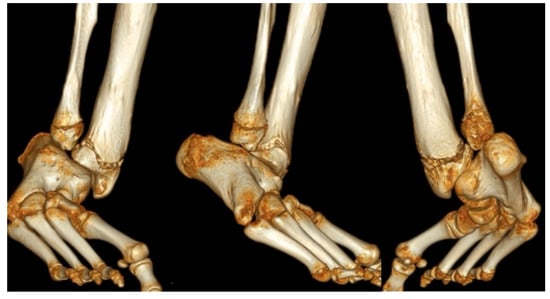

Figure 7.

(a) AP and lateral radiographs of 18-month-old girl with Paley type 3b1 FH. She has a rocker bottom foot and obvious subtalar coalition malunion. (b) Intraoperative fluoroscopic views showing splitting of subtalar coalition with an osteotome (left) and after shortening of tibia relative to fibula with plate fixation (SHORDT) combined with subtalar coalition malunion reduction and pinning. (c) Radiograph showing lengthening of tibia with computer dependent external fixator at the same surgery as the SUPERankle procedure. A hemiepiphysiodesis plate was also placed to treat the distal femoral valgus. (d) Final radiographs after removal of external fixator and after correction of proximal tibial valgus with a hemiepiphysiodesis plate. Note the stable appearance of the ankle joint and the plantigrade foot position. (e) Radiographic sequence of extramedullary lengthening with medially placed Precice nail (Nuvasive Specialized Orthopedics, California) (left). There is a Simple Locking IntraMedullary (SLIM) rod (Pega Medical, Montreal, Canada) and the fibula is fixed with tibio-fibular screws. The foot is fixed with a temporary extra-articular spanning screw from the foot to the tibia anterior to the ankle joint. A 5 cm lengthening was performed causing axial deviation into valgus bending the SLIM rod (middle). To correct the valgus, a plate was inserted laterally, and the extramedullary nail removed, after first decompressing the peroneal nerve, performing an anterior compartment fasciotomy and cutting the fibula proximally (right).